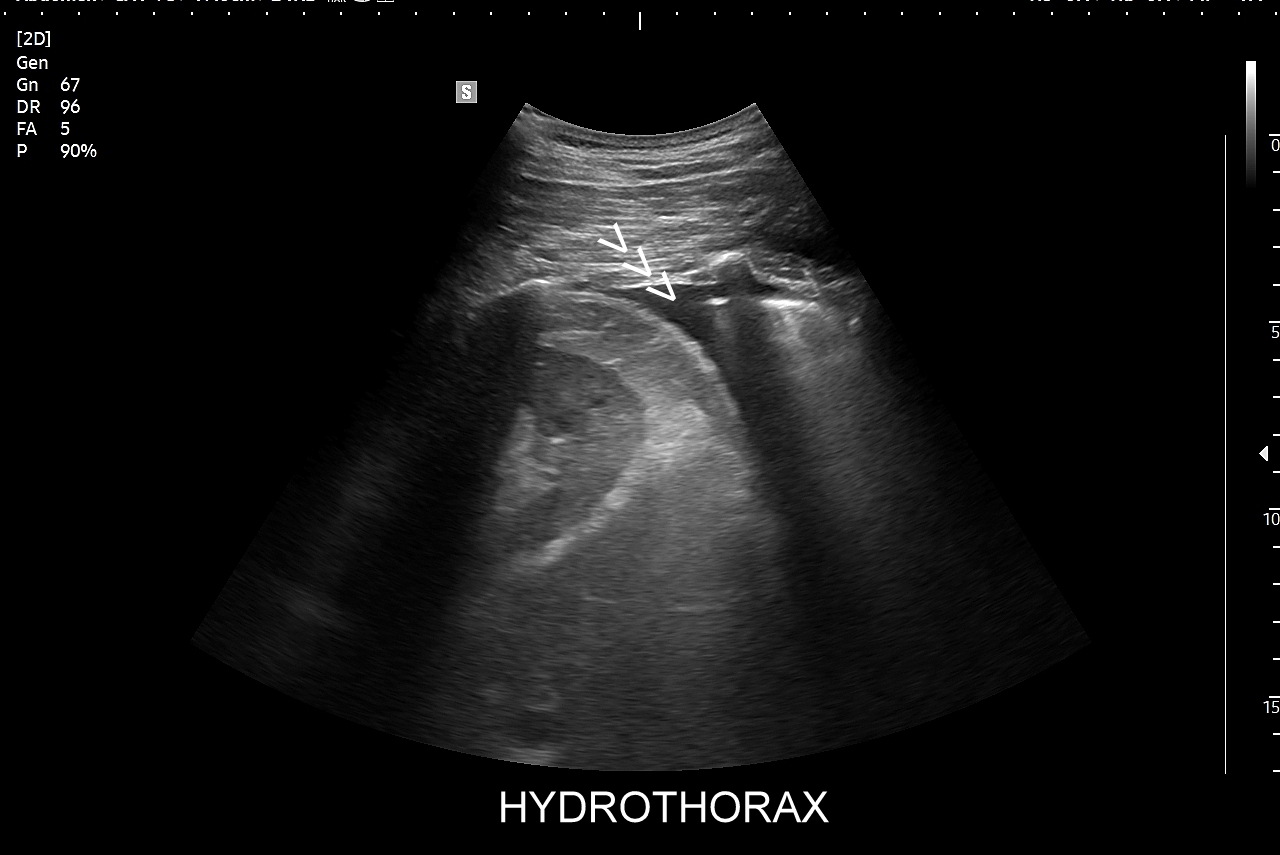

Wskazania do badania USG płuc są szerokie i obejmują m.in. szybkie męczenie się, zadyszkę, duszność, kłucie i ból w klatce piersiowej, a także w obrębie górnego i dolnego pogranicza klatki piersiowej (podstawa szyi, doły nadobojczykowe, podobojczykowe, pachy, okolica lędźwiowa, łuki żebrowe), zaostrzenie objawów astmy oskrzelowej lub przewlekłej obturacyjnej choroby płuc, nagłe zmniejszenie tolerancji wysiłku fizycznego, przedłużającą się lub nieskutecznie leczoną infekcję górnych dróg oddechowych, podejrzenie zapalenia płuc, monitorowanie leczenia zapalenia płuc, ocena po przechorowaniu zapalenia dolnych dróg oddechowych, w tym Covid, podejrzenie zaostrzenia niewydolności prawokomorowej lub lewokomorowej serca, w tym obrzęku płuc, podejrzenie odmy opłucnowej. Klasycznym wskazaniem do USG płuc i USG jam opłucnowych są oznaki obecności płynu, wysięku lub przesięku w jamach opłucnowych.

Kluczem do wartościowego zastosowania metody USG w diagnostyce pulmonologicznej jest zrozumienie jej możliwości oraz ograniczeń. USG jest niezwykle czułym badaniem w diagnostyce zapaleń płuc zarówno płatowych, jak i atypowych, np. wywołanych przez Mycoplasma lub Chlamydia. W przypadku zapalenia płuc pojawienie się widocznych zmian sonograficznych wyprzedza wystąpienie fenomenów osłuchowych wykrywanych przy osłuchiwaniu klasycznym stetoskopem. Metoda USG jest również bardzo czuła w diagnostyce chorób opłucnej i jam opłucnowych, takich jak nowotwory opłucnej, odma odma opłucnowa czy płyn w jamie opłucnowej. W rękach doświadczonego lekarza badanie USG może być przydatne w wykryciu zatorowości płucnej, a nawet guzów nowotworowych płuc.